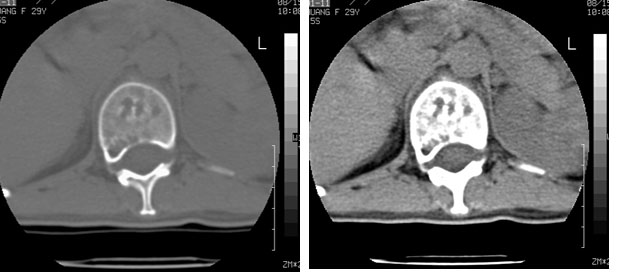

标题: CT10087:女,29岁,多发肿瘤样病变。

车祸致t12压缩性骨折,行ct扫描意外发现椎体多发肿瘤样病变,建议加拍骨盆平片,患者平常无症状。

考虑多发骨髓瘤可能性大。(骨松质内弥漫性分布,边缘清晰的溶骨性破坏,无硬化。睥脏增大,其内有多个圆形底密度影。淋巴瘤不除。

1:胸腰椎多发破坏伴骨折,近似穿凿样,考虑骨髓瘤,但有好多不符只出1、发病年龄小、女性,2、病变似有硬化环。2:淋巴瘤可能性大,骨及脾脏均有改变(脾脏改变似与外伤关系不大)建议密切结合临床及相关检验进一步诊断,期待结果。

椎体多发性溶骨性破坏,部分融合,椎旁无软组织肿块、椎间隙正常,t12 压缩,脾脏增大,其内示多发低密度影,首先考虑多发性骨髓瘤。病人较年轻,平素无异常,转移瘤可能性小。